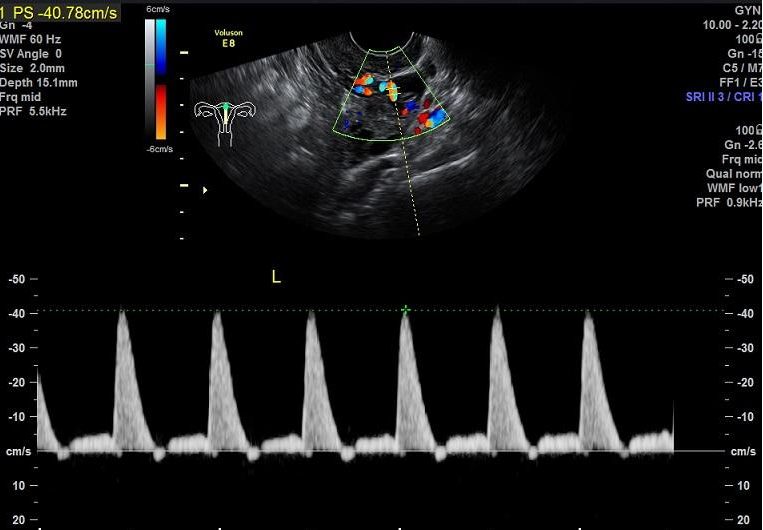

一项基于1700多例复发性流产患者进行的回顾性分析显示复发性流产有明确原因的达63%,排除胚胎因素后,自身免疫和血栓前状态导致反复流产者所占比例最大。而孕期的血栓状态最直接的影响就是子宫动脉血流,因此不少反复自然流产的患者伴有子宫动脉血流的异常。而我们通过B超可以很容易地了解到子宫动脉的血流情况。而最常见代表子宫动脉供血情况的参数包括搏动指数(PI)、阻力指数(RI)及收缩期峰值流速/舒张期流速(S/D)。

而子宫动脉血流指数在月经周期的不同时段会有所不同,正常情况下,排卵后的黄体期(受精卵着床时期)间子宫动脉的血流量增加,这对受精卵着床就非常有益。PI和RI值越低说明卵巢和子宫的血流灌注情况越好,胚胎着床率也就越高。

一般来说,在妊娠前子宫动脉血流动力学参数的正常范围是RI<0.85,PI<3,双侧S/D之和<12。